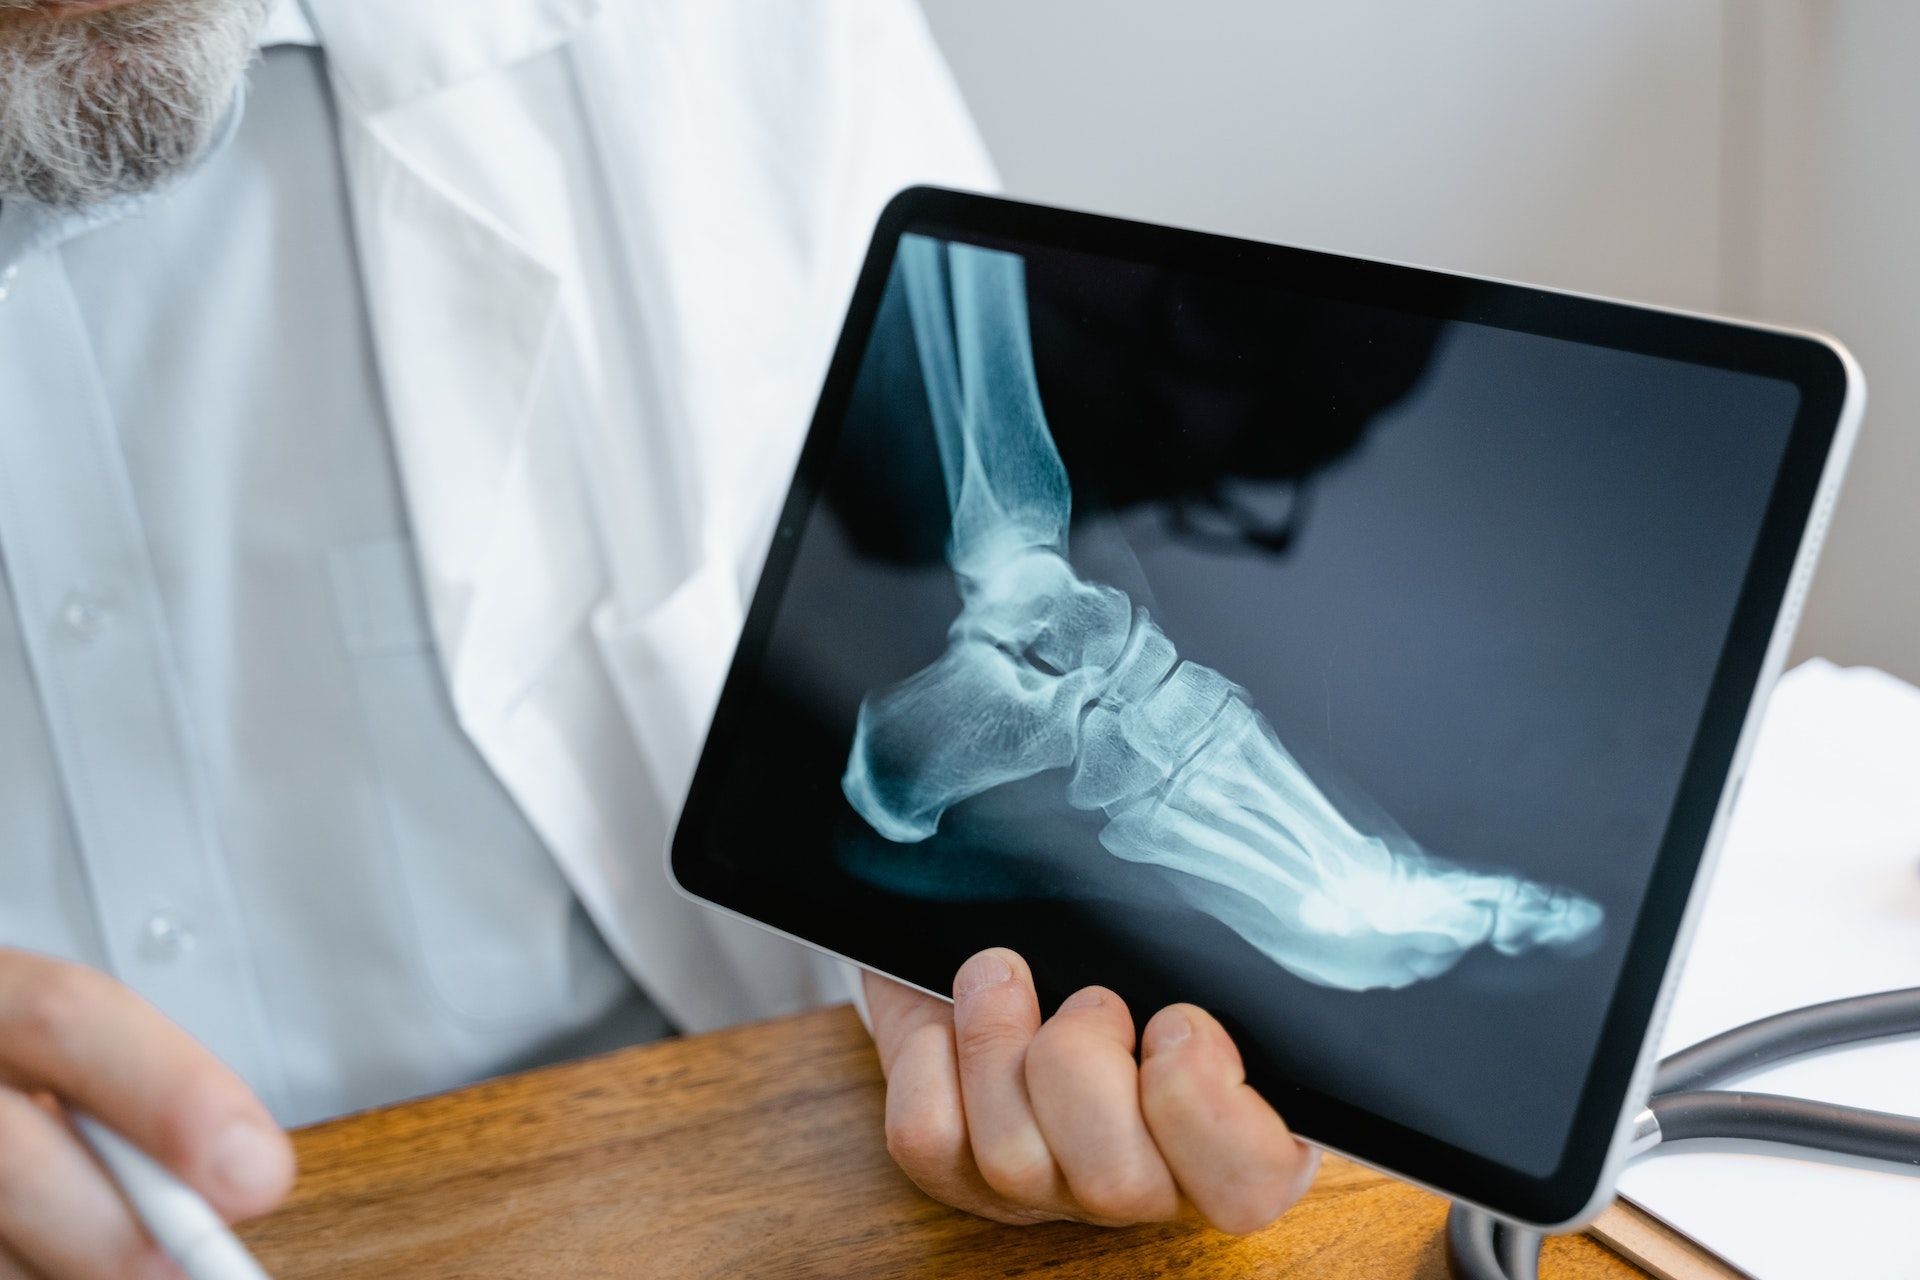

足底筋膜炎诊断方法

当患者脚底出现疼痛时,医生为了诊断是否为足底筋膜炎,会使用触诊,确认痛点是否在脚跟或脚跟内缘。

进一步的检查方式为超音波与X光检查,超音波可显示足底筋膜状况,若有足底筋膜炎征兆,足底筋膜会有增厚的情况;X光可观察足部骨骼结构,确认痛感是否来自骨骼或关节因素,以确诊足底筋膜炎。